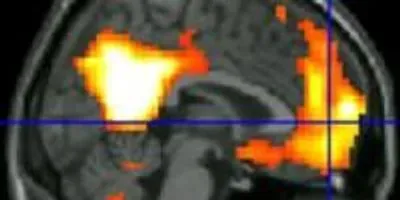

The colorful areas show the two brain regions where veterans trained in mindfulness saw the biggest increases in connections, using powerful fMRI scanners.Image courtesy of the University of MichiganThe changes showed up on functional MRI, or fMRI, brain scans that can visualize brain activity as different areas of the brain “talk” to one another through networks of connections between brain cells.

But after learning mindfulness, they developed stronger connections between two other brain networks: the one involved in our inner, sometimes meandering, thoughts, and the one involved in shifting and directing attention.

But at the end of the mindfulness course, the default mode area was more active–and showed increased connections to areas of the brain known as the executive network. This area gets involved in what scientists call volitional attentional shifting–purposefully moving your attention to think about or act upon something.

Those with the greatest easing of symptoms had the largest increases in connections.

“We were surprised by the findings, because there is thinking that segregation between the default mode network and the salience network is good,” says King. “But now we are hopeful that this brain signature of increased connection to areas associated with volitional attention shifting at rest may be helpful for managing PTSD, and may help patients have more capacity to help themselves get out of being stuck in painful ruts of trauma memories and rumination.”